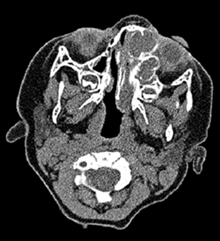

A 13-month-old patient was referred to the Oral and Maxillofacial Surgery Department of the La Paz Children’s Hospital with a fast-growing tumor located in the left nasomaxillary region. Regarding previous medical records, the mother and older brother suffered from Gardner’s syndrome. Computed tomography imaging was performed, showing a well-defined, insufflating osteolytic lesion located in the left nasomaxillary region, extending up to the left medial canthus, with the adjacent remodelling of the inferior orbital wall, left nasal bone, and protruding the ipsilateral eye. As a whole, the mass had a size of 31×23×48 mm, occupying the nostril (Figure 1). A nasoendoscopic biopsy was performed, suggesting a fibromyxoid tumor. After the results, radical resection was performed through an intraoral approach in the left maxilla, including a peripheral ostectomy and lateral nasal wall reconstruction with a PDS plate (Figure 2).

Figure 1: Preoperative computed tomography of the face with intravenous contrast.